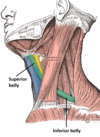

What is this muscle

The levator scapulae